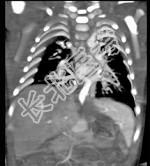

- 多项选择题女性,21岁, 活动后呼吸困难,时常发生上呼吸道感染, CT扫描如图所示,请选择正确的选项 ( )

A、考虑为肺静脉异位引流

D、该病人肺静脉异位引流入下腔静脉

E、该病人为心下型肺静脉异位引流